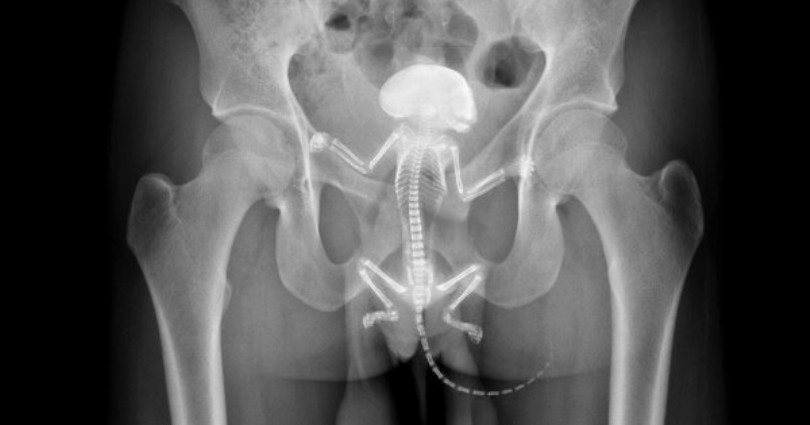

Man goes to the hospital because he has a squirrel inside

A man from New Hampshire had to be transported to the hospital this afternoon after his pet squirrel got stuck in his anal cavity.

Ray Frankfurt was transported to the Huggings Hospital in Wolfeboro, where doctors were able to extract the rodent.

Other images of things people have inserted into themselves